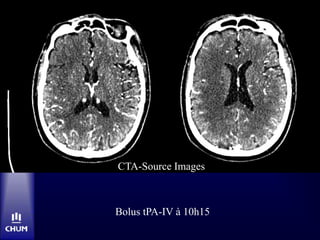

CT C- à 9h47

Bolus tPA-IV à 10h15

CTA-Source Images

Bolus tPA-IV à10h15 CTA-Source Images